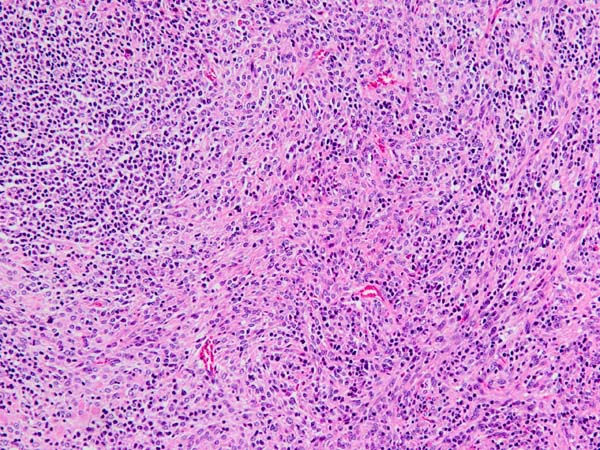

ワンちゃんが体調不良で来院されました。エコー検査で脾臓に大きな腫瘤が見つかったため飼い主様とご相談ののち摘出手術となりました。脾臓の病理組織検査の結果は「線維組織球性結節(グレード2)」でした。本疾患はリンパ球や組織球、線維芽細胞などの増殖を特徴とする病態で、肝臓へ転移する場合がありますので、定期的な経過観察が必要です。